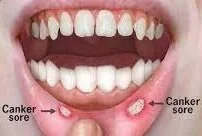

Mouth ulcers

Mouth ulcers are small, painful sores that develop on the inside of the mouth.

Mouth ulcers are usually not serious and will heal on their own within a week or two. However, they can be painful and uncomfortable, and may make it difficult to eat, drink, or talk. To help ease the pain and speed up the healing process, you can try: